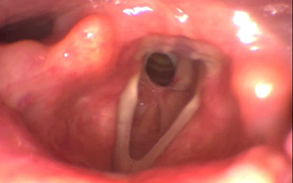

A 75-year-old female patient with no known pathological history, no surgical history. He came to our consultation referred by the pulmonology service due to progressive inspiratory dyspnea, laryngeal stridor with effort and rest, without dysphonia of 2 years of evolution, previously ruling out pathologies by pulmonology and cardiology. On physical examination, a nasofibrolaryngoscopy was performed, visualizing decreased subglottic lumen with good mobility of the vocal cords, normal mucosa and no laryngeal lesion. A stroboscopy is performed, visualizing subglottic stenosis of more than 60% of the glottic lumen (Figure 1), confirming with Computed Axial Tomography (Figure 2), reporting an infraglottic membrane that conditions slight reduction of the airway with the presence of a false lumen of 10 x 3 mm on the left side and 3 x 2 mm on the right side of the airway. In addition, complementary analytical studies to rule out inflammatory diseases as a possible cause, these being negative. He was scheduled to perform tracheostomy plus laryngeal microsurgery with CO2 laser resection and topical Mitomycin C. Pathological anatomy sample is sent reporting Fibro-leukocyte material, Subglottic Lesion. Currently exhaustive control by outpatient, patient is without dyspnea, without stridor and decannulated with more than 1 year post-surgery.